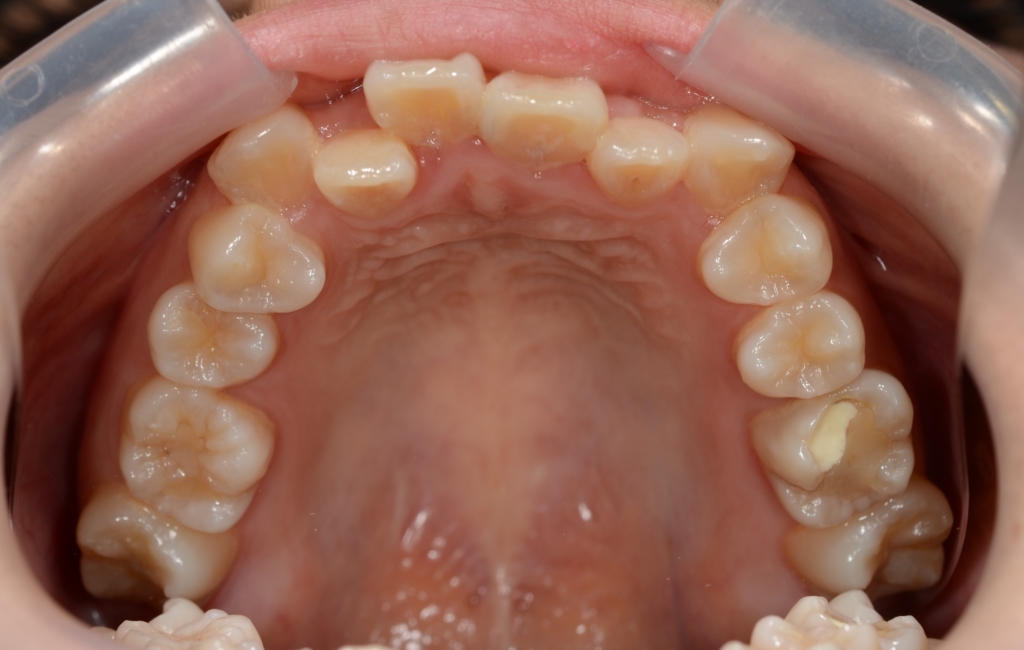

【Before】

レントゲン写真で確認すると、

この患者さんの場合、

#1.顎と歯の不調和による叢生

(前歯部の反対咬合を伴う)

#2.骨格的に下顎前突(受け口)傾向